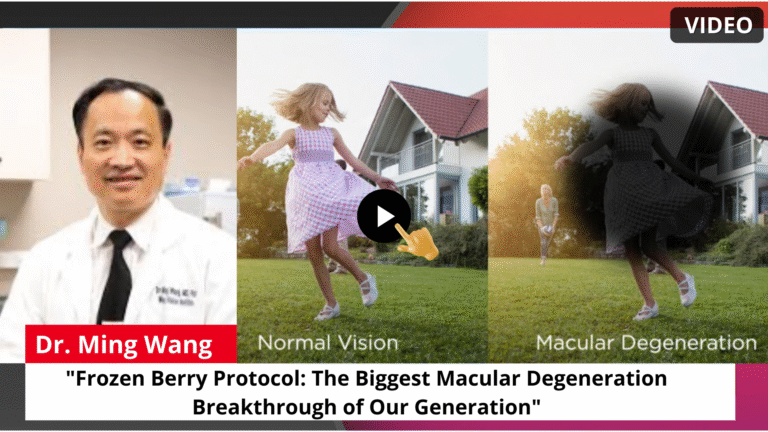

In the video, a renowned ophthalmologist reveals a “Frozen Berry Protocol” that works by dramatically increasing the eye’s own stem cell production — the natural repair cells responsible for rebuilding the damaged macula from the inside out. No surgery. No injections. No complicated routines.

A wave of new research from leading institutions has pinpointed a surprisingly simple reason why millions of Americans over 55 are losing their central vision — that dark, blurry patch right in the middle of their sight that makes reading, recognizing faces, and even watching TV feel impossible.

For decades, doctors have told macular degeneration patients the same thing: “We can slow it down, but we can’t reverse it.” Monthly eye injections costing up to $2,000 per eye. Endless follow-up appointments. And a quiet, terrifying feeling that total blindness is only a matter of time.